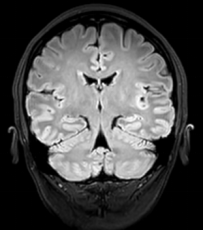

抗N-甲基-D-天冬氨酸受體腦炎的磁共振成像研究進展

脫髓鞘及自免腦二三事?2023-11-1619:29?發(fā)表于安徽編者薦語:抗NMDAR腦炎是自身免疫性腦炎中最常見的一種類型,其發(fā)病率逐年上升。臨床表現(xiàn)復(fù)雜多樣,診斷困難。近半數(shù)患者首次常規(guī)MRI有異常表現(xiàn),而高級MRI是加深對該病影像及病理和病理生理學(xué)認識的有效補充。抗N-甲基-D-天冬氨酸受體(N-methyl-D-aspartatereceptor,NMDAR)腦炎是自身免疫性腦炎(autoimmuneencephalitis,AE)最常見的一種類型。該病起病急,臨床癥狀重,近半數(shù)患者首次常規(guī)MRI有異常信號表現(xiàn)。不少研究認為,高級MRI是對該病影像學(xué)表現(xiàn)及病理和病理生理學(xué)認識的有效補充,可為其診斷及預(yù)后評估提供有效幫助。重慶醫(yī)科大學(xué)附屬第一醫(yī)院放射科羅天友教授團隊對近年來抗NMDAR腦炎MRI研究進展作一綜述,旨在提高對該病的認識。1臨床概述抗NMDAR腦炎為最常見的AE,約占所有AE的80%[1]。該病多見于兒童、青年,女性多于男性,目前全球報道的抗NMDAR腦炎發(fā)病率明顯上升,在青年人中其發(fā)病率甚至超過了病毒性腦炎(viralencephalitis,VE)[2,?3,?4]。研究發(fā)現(xiàn)有多種因素可觸發(fā)抗NMDAR腦炎的發(fā)生,并可分為伴腫瘤型與不伴腫瘤型。約25%的患者伴發(fā)腫瘤,這些腫瘤可以是卵巢畸胎瘤、小細胞肺癌、霍奇金淋巴瘤、慢性粒細胞白血病和子宮腺癌等[5,?6,?7,?8],其中卵巢畸胎瘤是抗NMDAR腦炎最常伴發(fā)的腫瘤,以成熟畸胎瘤多見[9,?10]。不伴腫瘤型可見于病毒和寄生蟲感染,也可見于炎性脫髓鞘患者,其中以單純皰疹病毒感染與其關(guān)系最密切[11,?12,?13,?14,?15]。此外,近期有文獻[16,?17]報道COVID-19感染合并抗NMDAR腦炎的病例??筃MDAR腦炎臨床表現(xiàn)復(fù)雜多樣,缺乏特異性,疾病過程大致可分為前驅(qū)期、精神癥狀期、反應(yīng)遲鈍期、多動期和恢復(fù)期五個不同階段。一般認為[18,?19,?20],前驅(qū)期通常以非特異性流感樣癥狀為特征;精神癥狀期可出現(xiàn)冷漠、焦慮、易怒、抑郁和恐懼等情緒改變;反應(yīng)遲鈍期和多動期可交替出現(xiàn),反應(yīng)遲鈍期常表現(xiàn)為緘默和反應(yīng)遲鈍,多動期主要表現(xiàn)為自主神經(jīng)功能障礙和異常運動;恢復(fù)期是一個緩慢的過程,恢復(fù)的順序常與癥狀出現(xiàn)的順序相反。約75%的患者可康復(fù)或僅遺留輕微后遺癥,另外25%的患者將會遺留嚴重殘疾甚至死亡[19]??筃MDAR腦炎的確診依賴于在患者腦脊液或血清中檢出相應(yīng)自身抗體。2常規(guī)MRI抗NMDAR腦炎的臨床表現(xiàn)缺乏特異性,確診依賴于抗體檢測,但其檢測費用高、耗時長、不易普及。T1加權(quán)成像(T1weightedimaging,T1WI)、T2加權(quán)成像(T2weightedimaging,T2WI)、T2加權(quán)液體衰減反轉(zhuǎn)恢復(fù)(fluid-attenuatedinversionrecovery,FLAIR)序列和增強掃描T1WI等常規(guī)MRI[21]對該病的早期診斷和預(yù)后評估有一定作用。據(jù)報道[22,?23,?24],約23%~50%的抗NMDAR腦炎患者首次常規(guī)MRI檢查顱內(nèi)可見異常表現(xiàn),異常信號可累及邊緣系統(tǒng)、大腦白質(zhì)和灰質(zhì)、小腦以及腦干,以海馬、額葉及顳葉多見。部分患者表現(xiàn)為腦內(nèi)散在異常信號,當邊緣系統(tǒng)受累時,病灶可對稱分布,而當白質(zhì)或深部灰質(zhì)受累為主時,病灶多不對稱,常呈斑片狀[25,?26]。部分患者以灰質(zhì)受累為主,表現(xiàn)為局灶性皮質(zhì)異常信號,相應(yīng)腦回腫脹,鄰近腦溝變窄[27]。個別病例可存在側(cè)腦室顳角擴大、垂體病變等[23]。抗NMDAR腦炎腦實質(zhì)病灶在T1WI上表現(xiàn)多不顯著,可呈等、稍低或低信號;T2WI上呈稍高或高信號;T2FLAIR序列病灶顯示最佳,常呈稍高或高信號[23]。增強掃描T1WI上,部分病灶可呈“腦回狀”或斑片狀強化,部分病灶強化不明顯,當累及腦膜時可表現(xiàn)為局部腦膜增厚或腦溝內(nèi)小血管影增多[26,?27]。有文獻[28]報道抗NMDAR腦炎的非典型病灶,如1例被誤診為韋尼克腦病的男性患者雙側(cè)額葉皮質(zhì)見條帶狀對稱性高信號及胼胝體壓部見對稱性“彩虹樣”高信號,鄰近腦回未見明顯腫脹;另1例患者雙側(cè)基底節(jié)區(qū)見對稱性斑片狀高信號,其MRI表現(xiàn)與肝豆狀核變性相似??筃MDAR腦炎常規(guī)MRI表現(xiàn)往往難以與AE的其他類型進行鑒別,有研究發(fā)現(xiàn)腦膜強化在抗NMDAR腦炎患者中更為常見,可作為急性期抗NMDAR腦炎與電壓門控鉀通道復(fù)合體抗體腦炎的鑒別點[29]。抗NMDAR腦炎常表現(xiàn)為彌漫性腦炎,而抗γ-氨基丁酸B型受體腦炎及抗富亮氨酸膠質(zhì)瘤失活1蛋白腦炎以邊緣葉受累為主[30]。抗NMDAR腦炎與VE的發(fā)病方式、臨床表現(xiàn)都很相似,但二者的治療方式和預(yù)后都不盡相同[31],常規(guī)MRI對早期鑒別診斷有一定價值。當病灶累及邊緣系統(tǒng)時,AE與VE病灶分布差異較明顯,AE病灶常呈對稱性分布,VE病灶常呈不對稱性分布[25]??傊?,常規(guī)MRI為診斷AE各亞型和與VE患者的鑒別診斷提供了有效的線索,對指導(dǎo)臨床治療有一定的意義。常規(guī)MRI表現(xiàn)異常與抗NMDAR腦炎患者的預(yù)后不良及復(fù)發(fā)相關(guān)。Lei等[32]發(fā)現(xiàn)常規(guī)MRI表現(xiàn)異常患者較常規(guī)MRI表現(xiàn)正?;颊叩暮喴字悄軝z查量表評分更低,表明常規(guī)MRI表現(xiàn)異常患者認知功能受損更嚴重;Balu等[33]發(fā)現(xiàn)MRI表現(xiàn)異常是抗NMDAR腦炎預(yù)后不良的獨立預(yù)測因子,并將此項納入他們構(gòu)建的診斷抗NMDAR腦炎1年后神經(jīng)功能預(yù)測評估表中。Zhang等[22]發(fā)現(xiàn)海馬受累患者隨訪期間改良Rankin評分明顯高于海馬未受累患者,認為海馬受累是抗NMDAR腦炎患者預(yù)后不良的重要預(yù)測因素;Feng等[34]應(yīng)用生存分析發(fā)現(xiàn)顱內(nèi)MRI病灶≥3個或腦干受累的抗NMDAR腦炎患者復(fù)發(fā)風(fēng)險更大。盡管僅有部分病例顯示異常表現(xiàn),常規(guī)MRI對抗NMDAR腦炎的診斷及預(yù)后評估仍有一定價值。當患者存在精神行為異常、癲癇發(fā)作、近事記憶障礙等神經(jīng)精神癥狀,MRI平掃顯示腦內(nèi)散在非特異性異常信號,增強掃描T1WI上病灶無強化或呈“腦回狀”、斑片狀強化,或出現(xiàn)腦膜增厚、腦溝內(nèi)小血管影增多等表現(xiàn)時,應(yīng)考慮到抗NMDAR腦炎的可能性。當常規(guī)MRI顯示病灶個數(shù)較多或海馬、腦干受累,應(yīng)加強患者管理,以有利于改善患者預(yù)后。3高級MRI3.1結(jié)構(gòu)成像結(jié)構(gòu)成像簡單易行,被廣泛應(yīng)用于探測多種神經(jīng)精神疾病較為隱匿的腦微結(jié)構(gòu)變化。形態(tài)學(xué)分析和容積分析作為常見的結(jié)構(gòu)成像方法,可進一步揭示抗NMDAR腦炎患者腦體積減小情況及其與認知的關(guān)系。Gomeze等[35]在一項縱向研究中應(yīng)用自動腦區(qū)分割法對25例抗NMDAR腦炎患者進行腦體積分析,發(fā)現(xiàn)患者腦總體積、小腦體積、腦干體積明顯減小。Xu等[36]對24例急性期后抗NMDAR腦炎患者進行基于表面的形態(tài)學(xué)分析以及海馬分割研究,發(fā)現(xiàn)患者語言網(wǎng)絡(luò)、默認網(wǎng)絡(luò)的相關(guān)腦區(qū)及左側(cè)海馬角的灰質(zhì)體積減小,而且這些改變與腦炎長期后遺癥引起的認知功能障礙有關(guān)。Bartels等[37]對38例兒童抗NMDAR腦炎患者進行容積MRI分析,發(fā)現(xiàn)隨著時間推移,有抗NMDAR腦炎病史的兒童患者表現(xiàn)出顯著的腦容量損失及皮層和皮層下灰質(zhì)減少所致的低于年齡預(yù)期的大腦發(fā)育異常。因此,當患者在隨訪過程中出現(xiàn)腦萎縮,提示更應(yīng)關(guān)注患者認知功能受損情況。由于結(jié)構(gòu)成像結(jié)果較為單一,常聯(lián)合應(yīng)用其他功能成像方法以全面揭示抗NMDAR腦炎的結(jié)構(gòu)與功能改變。3.2擴散成像擴散加權(quán)成像(diffusionweightedimaging,DWI)能檢測組織中水分子擴散運動受限的方向和程度,由于其敏感性高、掃描時間短,是臨床上最常使用的頭顱MRI功能成像序列。抗NMDAR腦炎大部分病灶DWI顯示為輕度擴散受限或擴散無明顯受限,多以稍高或等信號表現(xiàn)為主,部分病例局部腦回可呈高信號,表現(xiàn)為“皮質(zhì)綢帶征”[27,38]。但由于穿透效應(yīng)的影響,可能導(dǎo)致圖像出現(xiàn)假陽性表現(xiàn)。DWI上抗NMDAR腦炎信號改變?nèi)狈α炕瘶藴?,其表觀擴散系數(shù)值的價值有待今后進一步探討。擴散張量成像(diffusiontensorimaging,DTI)由DWI發(fā)展而來,能進一步量化水分子擴散運動中的各向異性,是評估腦白質(zhì)結(jié)構(gòu)變化的MRI技術(shù)。Phillips等[39]對46例抗NMDAR腦炎患者進行DTI研究,發(fā)現(xiàn)患者存在廣泛的皮層下白質(zhì)損傷,且這類損傷與患者持續(xù)性認知障礙相關(guān)。Liang等[40]利用DTI基于體素的分析和多變量模式分析也得出相似的結(jié)論,他們發(fā)現(xiàn)抗NMDAR腦炎患者右側(cè)顳中回、左側(cè)小腦中腳、右側(cè)楔前葉各向異性分數(shù)減低,左側(cè)顳中回和左側(cè)額葉平均擴散率升高,且這些改變與患者認知障礙相關(guān)。但DTI的原理是基于水分子服從高斯分布的假設(shè)[41],由于組織中細胞膜、神經(jīng)元和其他細胞器的存在,水分子的實際擴散服從非高斯分布,因此DTI的擴散參數(shù)不能準確描述水分子的擴散,尤其是富含神經(jīng)元細胞和樹突的灰質(zhì)中的水分子的擴散。未來可采用更高階的擴散成像技術(shù)進一步探討抗NMDAR腦炎患者腦灰質(zhì)的結(jié)構(gòu)變化,如擴散峰度成像[42]和神經(jīng)突起方向離散度與密度成像[43]。3.3灌注成像灌注成像通常采用動脈自旋標記成像(arterialspinlabeling,ASL)技術(shù)。ASL技術(shù)簡便,且可避免血腦屏障給示蹤劑帶來的阻滯作用,通過直接示蹤動脈血水分子運動以顯示腦血流灌注情況,從而提高了腦血流量(cerebralbloodflow,CBF)測量的準確性。Miao等[44]采用ASL研究發(fā)現(xiàn),急性期抗NMDAR腦炎患者左側(cè)島葉、左側(cè)顳上回、左側(cè)海馬、左側(cè)蒼白球以及雙側(cè)殼核和尾狀核CBF升高,雙側(cè)楔前葉和雙側(cè)枕葉CBF降低。同時,與健康對照組比較,存在精神行為異常的抗NMDAR腦炎患者左側(cè)島葉CBF減低,右側(cè)楔前葉、雙側(cè)距狀裂周圍皮層、雙側(cè)舌回的CBF升高,作者認為這些改變可作為抗NMDAR腦炎患者精神行為異常的預(yù)測因子。此外,研究發(fā)現(xiàn)恢復(fù)期抗NMDAR腦炎患者由于血管彈性下降,ASL檢查可顯示為全腦總CBF、左側(cè)中央前回以及雙側(cè)額下回CBF減低[45],提示恢復(fù)期患者即使臨床癥狀好轉(zhuǎn)仍存在血流灌注受損。因此,CBF檢測可以作為抗NMDAR腦炎患者早期診斷及監(jiān)測病情發(fā)展過程的指標之一。但該序列易受血液流動、磁化傳遞效應(yīng)等因素的影響,且對運動造成的誤差較為敏感,容易造成結(jié)果的偏差[46]。目前已開發(fā)出ASL的衍生技術(shù),如供血區(qū)ASL可對感興趣血管進行選擇性標記,3D-ASL可得到具有更高空間分辨率的影像,這些技術(shù)的應(yīng)用可從更細微、更直觀的角度探測抗NMDAR腦炎血流灌注的改變。3.4功能磁共振成像功能磁共振成像(functionalmagneticresonanceimaging,fMRI)主要分為任務(wù)態(tài)和靜息態(tài)fMRI,可為大腦功能和心理活動提供生態(tài)學(xué)上的有效視角,但由于無法客觀監(jiān)控受試者的行為任務(wù)表現(xiàn),不符合研究內(nèi)容的心理活動可能會導(dǎo)致結(jié)果的偏差。目前,將任務(wù)態(tài)fMRI應(yīng)用于抗NMDAR腦炎的研究較少。一項收集了抗NMDAR腦炎患者完成情景記憶任務(wù)時的數(shù)據(jù)的研究發(fā)現(xiàn),較健康對照組,在神經(jīng)水平上,患者在記憶編碼過程中表現(xiàn)出雙側(cè)海馬/海馬旁回、右側(cè)顳上回和右側(cè)丘腦更高的腦激活,而在行為水平上,患者的記憶功能表現(xiàn)較差。在記憶編碼過程中,左側(cè)海馬/海馬旁回的大腦激活程度越高,患者的記憶能力就越差[47]。這些觀察增強了我們對人腦中NMDAR功能障礙的理解。任務(wù)態(tài)fMRI能直接在受試者接受MRI掃描時評估其認知心理水平,但該方法更依賴于受試者的配合,實施難度更大,因此目前主要應(yīng)用靜息態(tài)fMRI方法研究抗NMDAR腦炎。靜息態(tài)fMRI可通過特定指標反映局部神經(jīng)元自發(fā)活動(neuronalspontaneousactivity,NSA)和腦功能活動(brainfunctionalactivity,BFA)的強度[48],功能連接(functionalconnection,FC)和局部一致性(regionalhomogeneity,ReHo)分析是常見的研究腦功能改變的方法。FC可檢測出不同空間位置腦區(qū)瞬間神經(jīng)活動的相關(guān)性[49],ReHo可反映局部腦區(qū)NSA在同一時間序列強度改變的相似程度[50]。Cai等[51]通過FC分析發(fā)現(xiàn),抗NMDAR腦炎患者的雙側(cè)扣帶回后部、左側(cè)楔前葉、雙側(cè)小腦的NSA和BFA減低,且這些改變與認知障礙和情緒調(diào)節(jié)受損相關(guān);他們還發(fā)現(xiàn)雙側(cè)扣帶回后部與初級視皮層的FC升高,并認為這可能是機體通過增強與記憶相關(guān)的視覺腦區(qū)的活動來代償改善記憶功能所致。Li等[52]利用fMRI構(gòu)建了一個功能性網(wǎng)絡(luò),通過分析網(wǎng)絡(luò)參數(shù)的拓撲結(jié)構(gòu),發(fā)現(xiàn)島葉是抗NMDAR腦炎患者功能性腦網(wǎng)絡(luò)的中樞,其FC受損影響了頂葉的功能,從而干擾信息的維持、傳輸和反饋,導(dǎo)致患者認知能力下降。Wu等[53]應(yīng)用ReHo分析結(jié)合多變量模式分析發(fā)現(xiàn),抗NMDAR腦炎患者雙側(cè)小腦后葉、小腦前葉、頂下小葉、中腦、尾狀核及右側(cè)額上回、顳中回、左側(cè)額中回的ReHo值降低,他們還建立了抗NMDAR腦炎患者的全腦ReHo模式空間分布特征,此分類模型的準確率可達76.83%。此外,結(jié)合機器學(xué)習(xí)算法(如隱馬爾可夫模型)研究FC在時間上的波動,以此研究大腦動力學(xué)的方法是當前的研究熱點[54,?55],但該方法目前尚未應(yīng)用于抗NMDAR腦炎的相關(guān)研究中。3.5磁共振波譜磁共振波譜(magneticresonancespectroscopy,MRS)分析可在活體內(nèi)檢測生化和代謝物質(zhì),可早期檢測到腦代謝異常?;?H的MRS技術(shù)在腦科學(xué)研究中應(yīng)用較多,常用于腦損傷、腦瘤等疾病的診斷和分級,但抗NMDAR腦炎的相關(guān)研究中應(yīng)用較少,多以個案形式報道[56,?57]。既往報道的抗NMDAR腦炎患者的MRS信號特征相似,其異常信號區(qū)較對側(cè)正常腦組織比較,均表現(xiàn)為N-乙酰天冬氨酸(N-acetylaspartate,NAA)峰降低,膽堿(choline,Cho)峰升高,導(dǎo)致Cho/NAA比例倒置。NAA峰的降低提示神經(jīng)元功能活動減低,Cho峰升高提示細胞破壞或細胞密度增高[58],但此類特征也可見于炎癥、感染和腫瘤性疾病,特異性較低。目前MRS對抗NMDAR腦炎的診斷價值有待進一步評估,未來還需更大規(guī)模的臨床試驗以提高對該病的認識。但由于需要預(yù)先設(shè)置感興趣區(qū),MRS難以檢測全腦廣泛的代謝改變,可結(jié)合其他適用于全腦的高級MRI,以發(fā)現(xiàn)腦內(nèi)的微小改變。3.6影像組學(xué)和深度學(xué)習(xí)影像組學(xué)和深度學(xué)習(xí)是目前的前沿?zé)狳c,可挖掘病灶和全腦的深層特征,但模型的泛化能力很大程度依賴大樣本的數(shù)據(jù),而抗NMDAR腦炎屬于罕見病,收集相對困難。多中心研究可在一定程度上解決該問題,然而目前應(yīng)用此類方法的抗NMDAR腦炎相關(guān)研究仍極少。Xiang等[59]建立了一個結(jié)合臨床變量、深度學(xué)習(xí)和影像組學(xué)特征的融合模型,以預(yù)測成人抗NMDAR腦炎患者的早期功能結(jié)果。他們開發(fā)了用單個或組合的4個臨床MRI序列(T1WI、T2WI、T2FLAIR序列和DWI序列)訓(xùn)練的5個深度學(xué)習(xí)和放射組學(xué)模型,以及一個用臨床變量訓(xùn)練的臨床模型,以預(yù)測抗NMDAR腦炎的預(yù)后。結(jié)果顯示融合模型的預(yù)測性能顯著優(yōu)于單獨的深度學(xué)習(xí)、影像組學(xué)和臨床模型。與所有單序列模型相比,深度學(xué)習(xí)和影像組學(xué)的多序列模型具有更高的受試者操作特征曲線下面積值和準確度。綜上所述,高級MRI進一步發(fā)現(xiàn)和解釋了部分抗NMDAR腦炎患者常規(guī)MRI表現(xiàn)正常而臨床癥狀嚴重或預(yù)后較差的原因。這些技術(shù)各有優(yōu)缺點,合理聯(lián)合應(yīng)用各項技術(shù)是加深對該病影像學(xué)表現(xiàn)及病理和病理生理學(xué)改變的認識的有效補充,如Wang等[60]應(yīng)用形態(tài)學(xué)分析方法結(jié)合DTI和fMRI構(gòu)建了抗NMDAR腦炎的多模態(tài)網(wǎng)絡(luò)中發(fā)現(xiàn),抗NMDAR腦炎患者功能網(wǎng)絡(luò)僅有細微變化,而形態(tài)網(wǎng)絡(luò)和結(jié)構(gòu)網(wǎng)絡(luò)改變較為顯著,為抗NMDAR腦炎提供了特征性多模態(tài)網(wǎng)絡(luò)功能障礙的全面視圖。4總結(jié)和展望抗NMDAR腦炎是一種發(fā)病率逐年上升的自身免疫性疾病,可伴發(fā)于腫瘤(以卵巢畸胎瘤多見)或繼發(fā)于感染性病變(以單純皰疹病毒性腦炎多見),臨床表現(xiàn)復(fù)雜多樣,確診依賴于在患者腦脊液和(或)血清中檢出相應(yīng)自身抗體。近半數(shù)患者首次常規(guī)MRI有異常信號表現(xiàn),但缺乏特異性。高級MRI技術(shù)可從多角度揭示抗NMDAR腦炎的病理和病理生理學(xué)改變,有助于提高對該病的認識。然而,目前對抗NMDAR腦炎研究的樣本量均不大,大部分研究也未對不同病程、不同用藥方式進行分組,未來應(yīng)著眼于在大樣本的基礎(chǔ)上,采用多模態(tài)多參數(shù)MRI技術(shù)進行深入研究。作者利益沖突聲明:全體作者均聲明無利益沖突。參考文獻略?!緞⒑o,羅天友.抗N-甲基-D-天冬氨酸受體腦炎的磁共振成像研究進展[J].磁共振成像,2022,13(9):139-143.?DOI:10.12015/issn.1674-8034.2022.09.033.】(作者:劉涵靜,羅天友)